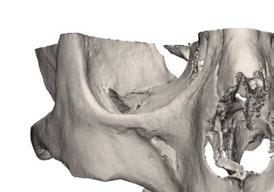

Este caso clínico es un premolar que tiene 3 conductos: sabemos que 2 de ellos son en la raíz vestibular, y

en el CBCT podemos apreciar a qué longitud del conducto se produce la bifurcación (Figura 10)

Debido a la gran curvatura que se produce en la bifurcación, tenemos que precurvar los instrumentos manuales y rotatorios, para facilitar que los instrumentos alcancen la LT (Figura 11). Terminamos el conducto mesiovestibular y palatino en conicidad .06 y el disto-vestibular en .04 debido al riesgo que pensamos que correríamos si hacemos una secuencia más amplia.

Figura 10. Estudio Radiográfico en 2D y 3D del caso clínico. Figura 11. Secuencia operatoria que realizamos en cada uno de los conductos. Figura 12. Secuencia realizada para la obturación con onda continua.